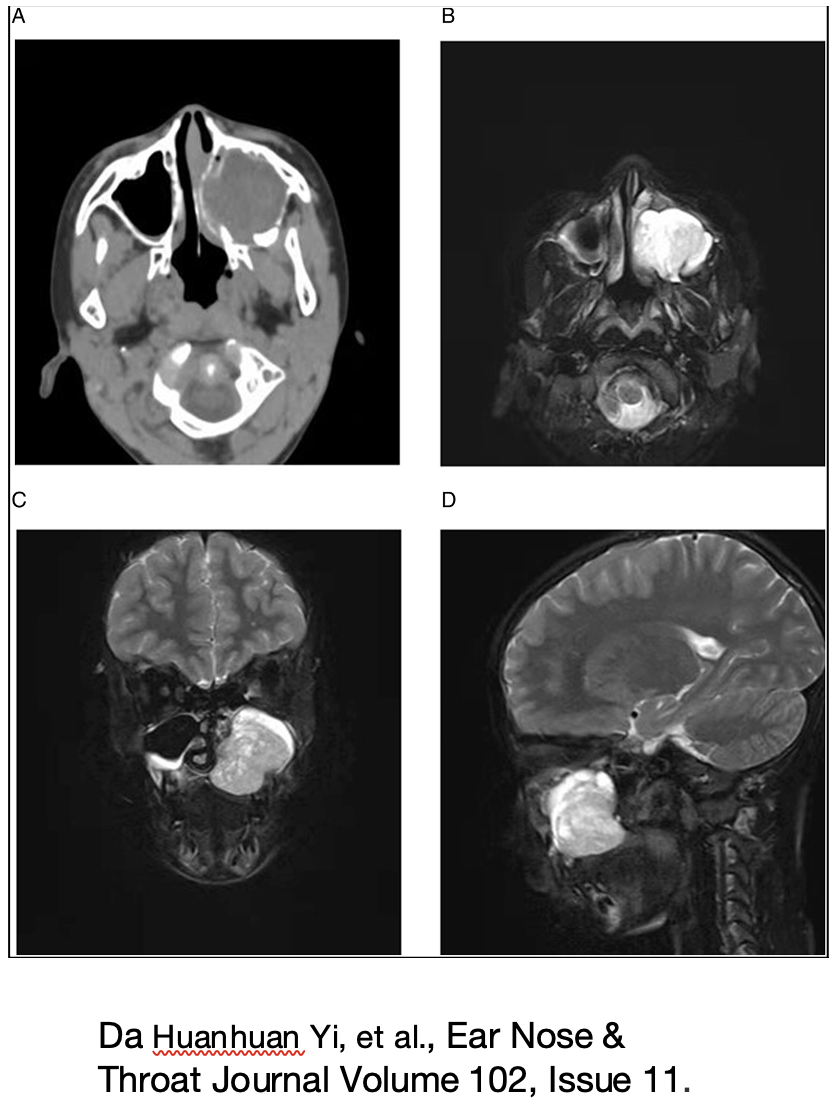

TAC e MRI sono gli esami diagnostici di routine anche nell’infanzia per visualizzare l’estensione (basso segnale in T1 e alta presa di contrasto in T2 alla RM), erosioni delle limitanti ossee e l’iperostosi da cui generalmente prende origine SNIP.